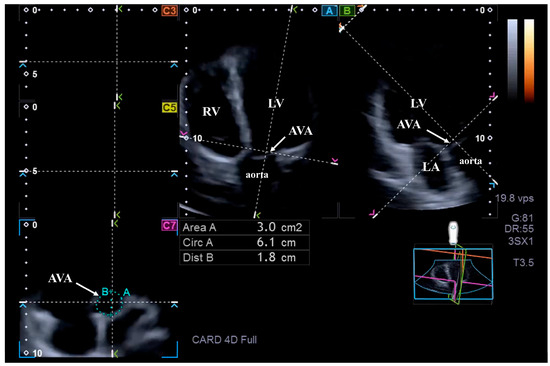

Background: Acromegaly, typically caused by growth hormone (GH)-secreting pituitary adenomas, leads to chronic GH and insulin-like growth factor-1 overproduction, resulting in significant cardiovascular complications, including left ventricular (LV) hypertrophy, myocardial fibrosis, diastolic/systolic LV dysfunction, and frequent valvular disease. Although aortic root dilation has been documented, the morphology and function of the aortic valve annulus (AVA) and its relationship with LV performance remain unexplored. Methods: The present study comprised a total of 31 patients with acromegaly, from which eight subjects were excluded due to inferior image quality. The remaining group of acromegalics consisted of 23 cases (mean age: 54.3 ± 14.5 years, 6 males). Their results were compared to 31 age- and gender-matched healthy subjects (mean age: 50.0 ± 7.4 years, 9 males). Cardiac assessment involved routine two-dimensional Doppler echocardiography and three-dimensional speckle-tracking echocardiography (3DSTE) to quantify basal regional and global longitudinal strains. Detailed planimetric measurements of AVA dimensions and its spatial displacement, called AVA plane systolic excursion (AAPSE), were also obtained. Results: Among 12 patients with inactive acromegaly, 7 patients (58%) showed larger end-systolic AVA area (AVA-A), while 5 patients (42%) had larger end-diastolic AVA-A. Among the 11 patients with active acromegaly, 3 patients (27%) had larger end-systolic AVA-A and 5 patients (45%) had larger end-diastolic AVA-A, while in 3 patients (27%) end-systolic and end-diastolic AVA-A proved to be equal. All end-systolic and end-diastolic AVA dimensions were tendentiously greater in acromegaly, with more pronounced values seen in the presence of an active disease. AAPSE was reduced both in all acromegaly patients and in those with active disease compared to controls. From LV strains, basal and global LV longitudinal strain (LS) and basal LV circumferential strain (CS) were similar when comparing acromegaly patients and those with active and inactive disorder to controls. However, basal and global LV-LS tended to be reduced, while basal LV-CS tended to be increased. Significantly increased global LV-CS were present in active acromegaly patients compared to inactive acromegaly patients and controls Conclusions: Significant aortic valve annular dilation is present in acromegaly, which is associated with its reduced spatial systolic displacement. Full article

Figure 1